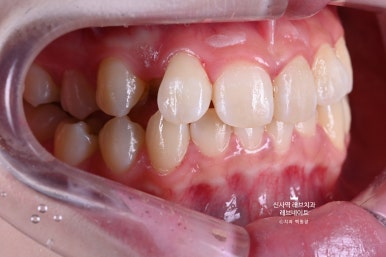

그냥 얼핏 보기엔 뭐.. 치열이 조금 틀어져 있네? 이 정도라고 생각이 드실텐데요

(저 또한 그랬습니다.)

이게 왠걸 ! 고개를 돌려보니 치아가 하나 없는겁니다...

어딨지? 하고 보니,

오른쪽 송곳니가 보다 안쪽에 있는 부정교합이라, 마치 치아하나가 없는 것 처럼 보이는 상태셨어요.

정면만 딱 보면 안보이는 것 같은데, 얘기하거나 웃을 때 엄청 잘 보이는 앞니 사이 공간이 있는거에요..

그리고 잘 보면, 치아들이 조금 뻐드러져 있기도 하고.. 뭔가 돌아가 있기도 하고..